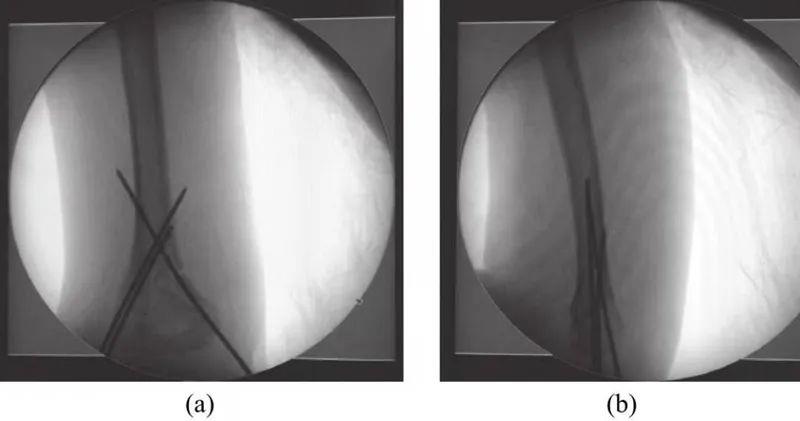

(2)Ⅱ型肱骨髁上骨折:手法整复矫正肘关节过伸和成角畸形是治疗此型骨折的关键问题,虽然闭合复位后,可用石膏托或支具的过曲位(肘关节屈曲120°)固定维持整复后的位置,但却增加患肢神经血管损伤的及并发急性筋膜间隔综合征的危险,因此骨折闭合复位后最好行经皮克氏针内固定(图1),而后用石膏托外固定于安全体位(肘关节屈曲60°)。

图1 经皮克氏针内固定图像

骨折闭合复位后克氏针固定的方式和最佳的数目也存在不同观点。编者的经验是克氏针固定时应彼此呈分岔状,在骨折平面彼此间隔越远越稳定,克氏针不应在骨折平面交叉,否则不能控制旋转且固定不牢靠。采用内侧克氏针固定时应注意避免损伤尺神经。不要在肘关节屈曲位置时穿针,需稍伸直肘关节以使尺神经后移,用拇指触及尺神经并将其推向后方后安全穿克氏针。应用交叉克氏针内固定对于术后功能康复、骨折愈合率、骨折愈合优良率等具有潜在的优势,这有利于术后早期康复。